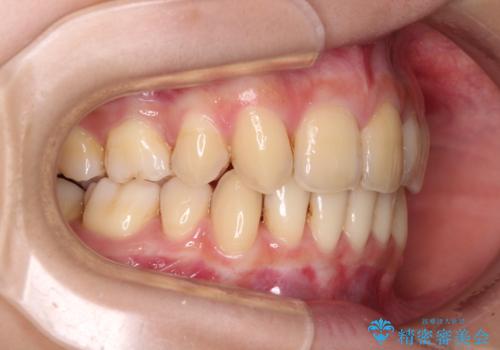

出っ歯を治したい ワイヤー装置による抜歯矯正

- 上下の出っ歯を気にして来院された患者様です。

口元を積極的に引っ込めるために、上下左右の小臼歯を4本抜歯することとしました。

右上前から2番目の歯が欠損しているため、①矯正治療により欠損部にスペースを作りインプラント補綴を行って前歯を左右対称に揃える、②左右非対称となるが、欠損補綴を行わずに排列する、のいずれかとなりますが、患者様と相談の上②にて矯正治療を行うこととしました。

変則的な歯列であったため、奥歯がしっかりと咬み合うのか、前歯はしっかりと排列できるのかと不安ではありましたが、結果としてはきれいに整った歯列にて終了することができました。